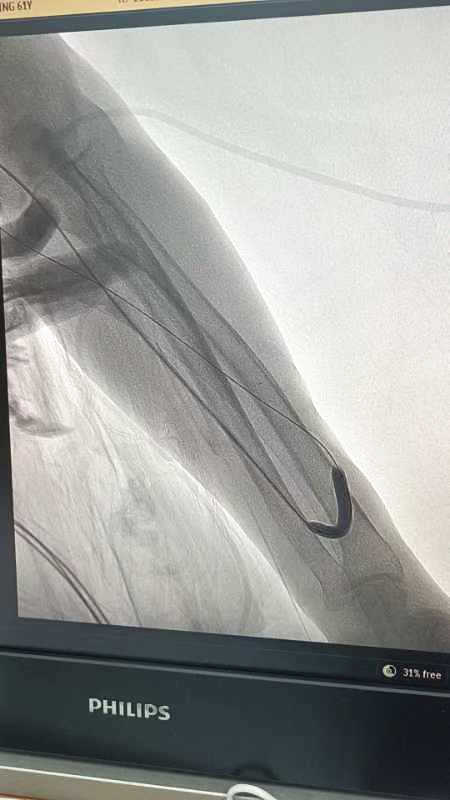

扩张后造影

经过充分的术前准备,手术如期进行。在超声引导下,医生将球囊送至患者血管狭窄处,通过缓慢加压使狭窄部位得到充分扩张,从而恢复了血管内径。整个手术过程无开放性伤口,极大地保护了患者有限的血管资源。术后,患者内瘘狭窄得到再通,血流量恢复正常,透析得以顺利完成。